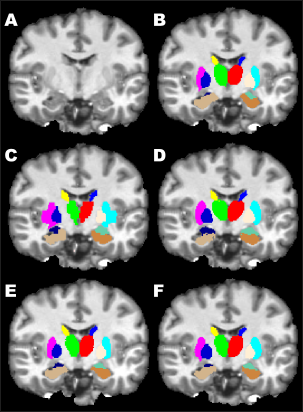

Figure 3 shows a qualitative comparison of segmentation outputs from FreeSurfer, FIRST, PICSL, and our method. As it can be observed, FreeSurfer provided the worst segmentation output with coarse structure boundaries. FIRST produced smooth segmentation on the borders, however, the overlap between the groundtruth was poor. Our method’s segmentation output was similar to the one of PICSL’s and both of the methods had consistent structure boundaries, which were not far from the groundtruth.

Refer to caption

Figure 3: Qualitative comparison of segmentation outputs obtained by FreeSurfer, FIRST, PICSL, and our method on MICCAI 2012 dataset. A) T1-w image; B) Groundtruth; C) FreeSurfer; D) FIRST; E) PICSL; F) Our method. Visible structures on coronal view: thalamus, caudate, pallidum, putamen, hippocampus, and amygdala.